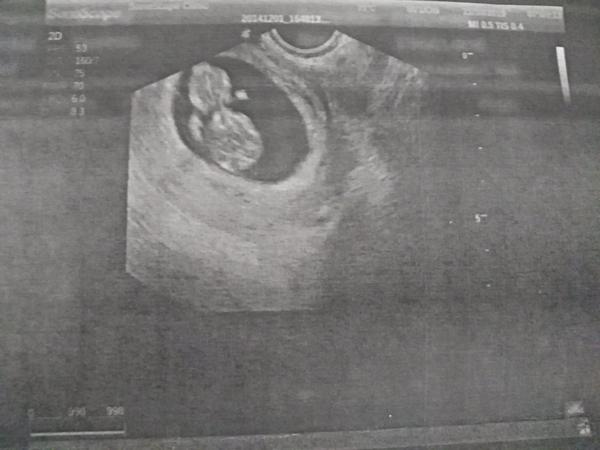

@racochejlek87 V 6tt uz bilo a ted sem byla 7+6 a taky busilo krasneeee

Ahoj holky, tak dalsi kontrola zamnou a vse v poradku 😍